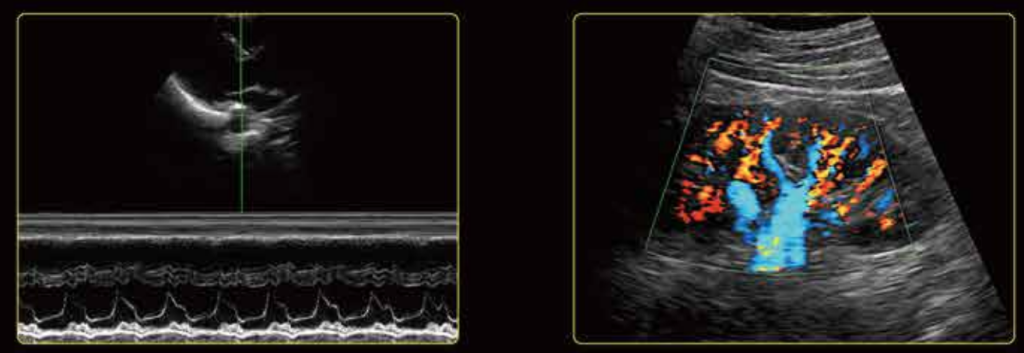

Шикарное качество изображения

U60 обеспечивает отличную детализацию, контрастное разрешение и равномерное изображение без ущерба для глубины проникновения. Превосходная цветопередача и чувствительность Допплера легко обнаруживают небольшие сосуды с низким кровотоком. Сонная артерия и правая печеночная вена

Сонная артерия и правая печеночная вена Митральный клапан и сосуды почек

Митральный клапан и сосуды почек Плечевое нервное сплетение и пупочная артерия